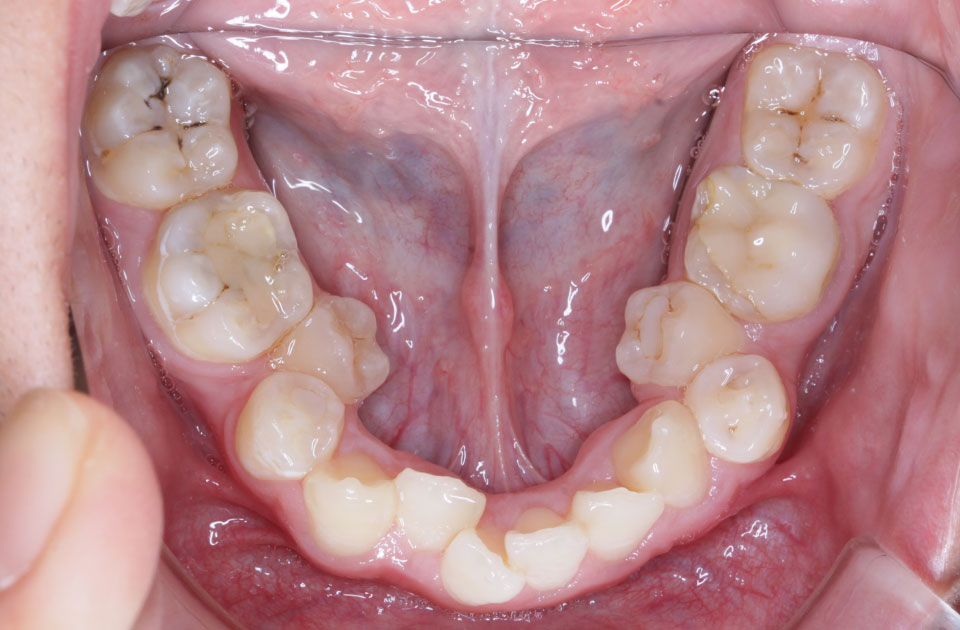

矯正前 下顎

主訴 凸凹の歯並びを治したい。虫歯が多い。

年齢 10代男性

抜歯の有無 上顎左右第一大臼歯、上顎左側第一小臼歯、下顎左右側第一大臼歯